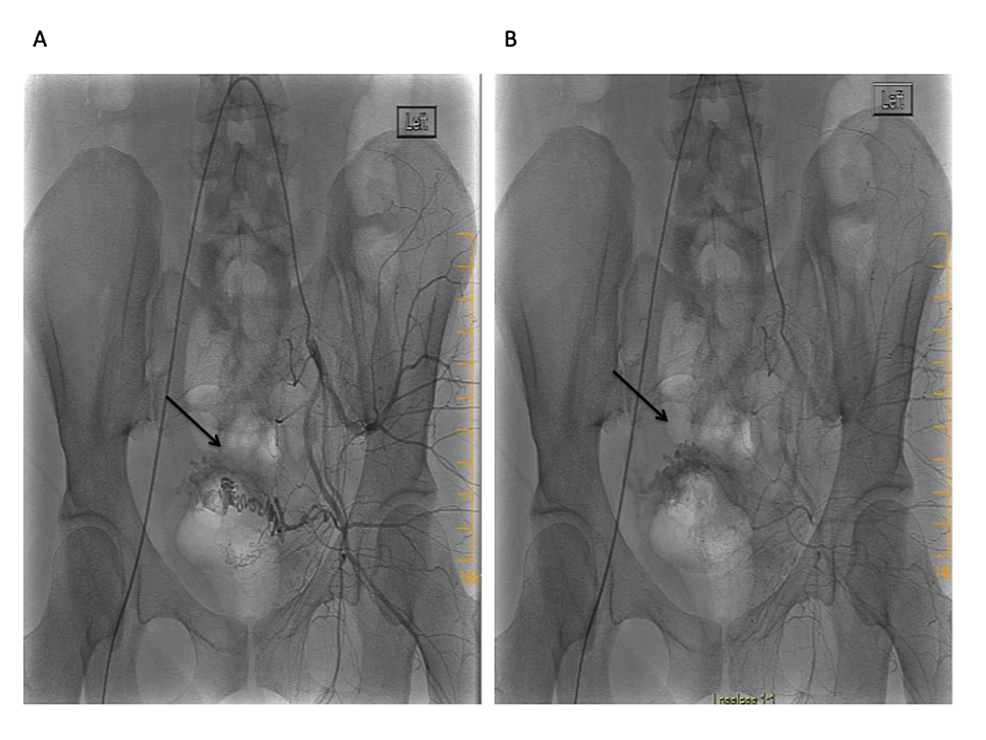

Taken together, a presumptive diagnosis of the uterine AVM was made and the patient was referred to interventional radiology. The uterine angiogram confirmed the presence of an AVM within the posterosuperior wall (Figure 4). There were multiple feeding arteries mainly from the left with smaller arteries from the right. Embolization of both uterine arteries was performed with Gelfoam (Pfizer, New York, USA) pledgets to near stasis. The post-embolization arteriogram showed complete embolization of the AVM with slow flow of contrast in both uterine arteries. No immediate complications were encountered. The patient's vaginal bleeding resolved and she was discharged three days later. No recurrence of abnormal uterine bleeding was reported at either the three-week or six-month follow-up visit.